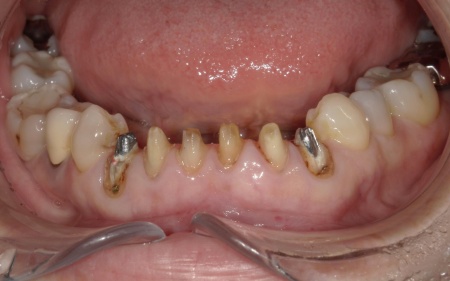

60代女性 古い被せ物を作り直して審美性を改善させた症例

「20年前、受け口を改善するために審美歯科で被せ物による治療を受けたが、仕上がりに不満が残った。最近、再び気になるようになったため、再治療が可能かを相談したい」とご相談いただきました。

拝見したところ、上下前歯には金属製の土台「メタルコア」を使用した被せ物(クラウン)が装着されており、被せ物と歯茎の境目付近が黒くなっていました。

被せ物の土台がメタルコアの場合、以下のような理由から歯茎との境目が黒く見えることがあります。

・メタルコアから溶け出した金属成分が歯茎に沈着し、黒色〜青黒色に見えることがある

・歯茎が薄い方の場合、土台の金属色が透けて暗く見えることがある

・土台を作製したり形を整えたりする時に生じた金属の細かな粉が歯茎に入り込み、黒い点として見えることがある(メタルタトゥー)

そのため、黒ずみの原因であるメタルコアを除去する治療が必要でした。

また、保険適用の白い詰め物(コンポジットレジン)が充填されている部分には変色が見られます。ご自身の歯、被せ物、コンポジットレジン、それぞれの色調が異なっていることで審美性に影響が出ているため、上下前歯(合計12本)の被せ物と詰め物を新しくする必要があると診断しました。

また、左上前歯2本と左右下前歯2本は、細菌感染した神経を取り除いてから薬を詰める「根管治療」が施されていましたが、薬が歯根の先までしっかり詰められていなかったため、「再根管治療」が必要であることも併せてお伝えしています。